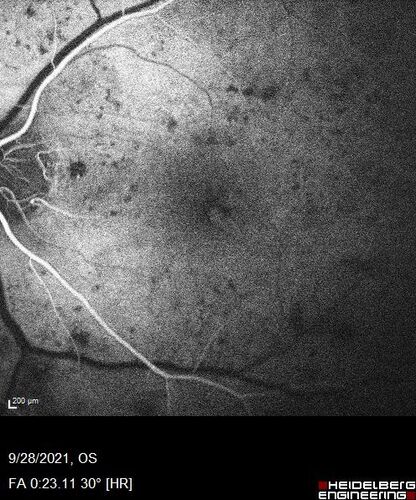

Nonproliferative Diabetic Retinopathy and Good Vision

59 year old man Vision is good.  Just referred following annual eye examination

PMHx: Type II DM, HTN, Cholesterol,

MEDS: Lantus, Metformin, lisinopril, atorvastatin, gabapentin

VA 20/20 OU

2+ NS OU

Observation